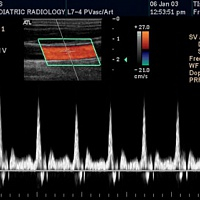

- CW доплер

- Режим тканевой гармоники

- Технология подавления артефактов зависящих от угла обзора: SonoCT

- Категории пациентов: Взрослые, дети, новорожденные